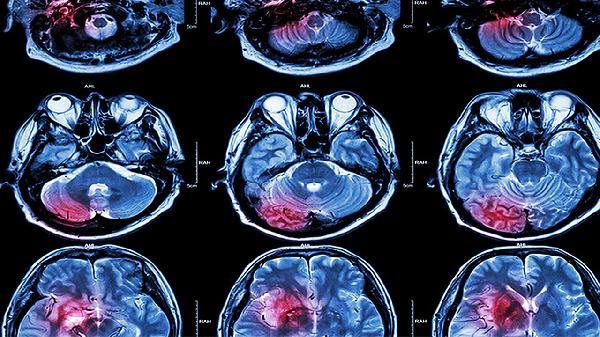

脑血栓形成的原因主要有动脉粥样硬化、高血压、心脏病、血液高凝状态和脑血管畸形等。脑血栓通常表现为肢体麻木、言语不清、头晕头痛等症状,需及时就医干预。